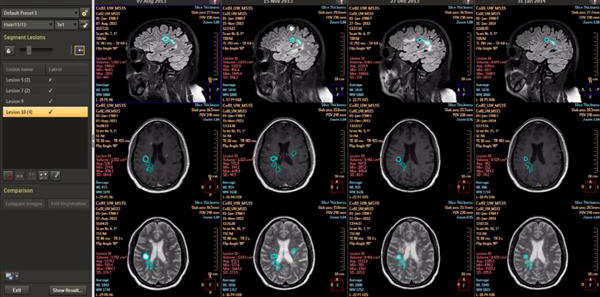

通過新的機器學習能力,IntelliSpace Portal 9.0用縱向腦成像(尚未批準在美國使用)等功能幫助放射科醫(yī)生檢測、診斷疾病并跟進疾病的治療??v向腦成像被用來對神經障礙進行縱向評估,這種持續(xù)監(jiān)測功能使得臨床醫(yī)生可以跟蹤疾病的發(fā)展狀況。IntelliSpace Portal 9.0上還有CorTech Labs的測量應用程序NeuroQuant,臨床醫(yī)生可用它來確定腦體積的損失量。